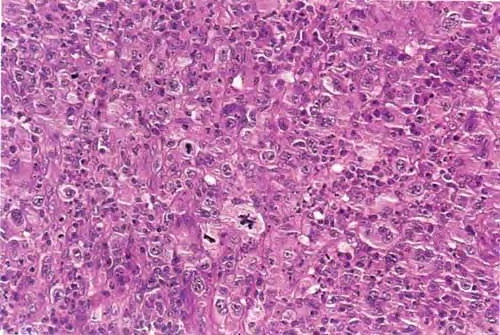

Large cell anaplastic lymphoma= اللمفوما فاقدة التمايز كبيرة الخلايا